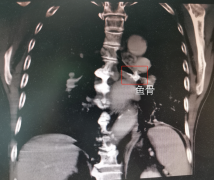

凯发线上登陆下载:广东一老伯鱼骨卡气管近60年没取,医生:实